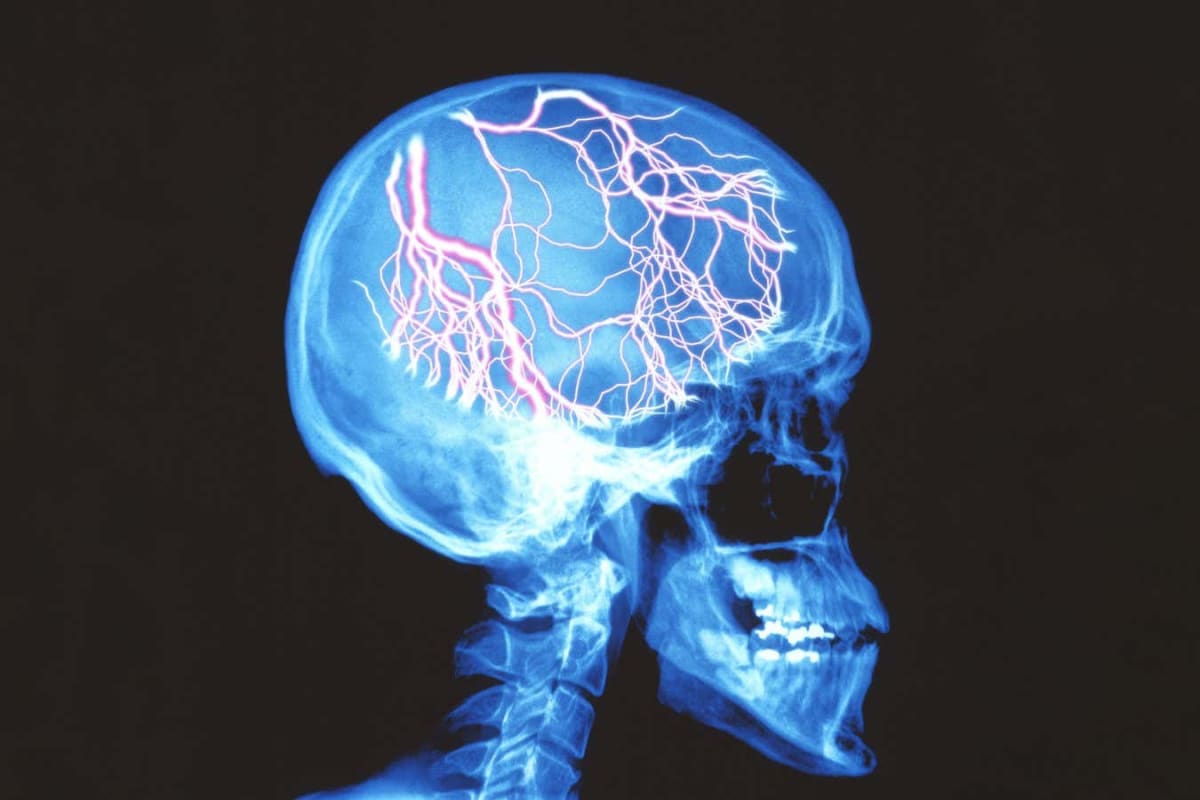

The secret appears to lie in the brain's glymphatic system, a waste disposal network that flushes out harmful chemicals. CGRP impairs this cleaning system, but prazosin reverses that damage and helps sweep away pain-causing molecules.